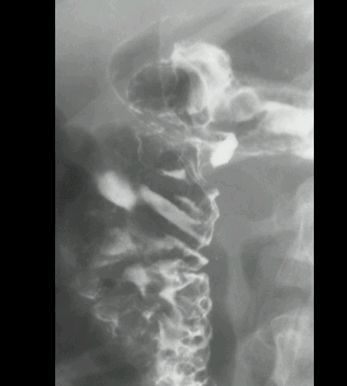

UCHYŁEK PRZEŁYKU

KONTRAST DO GOPP